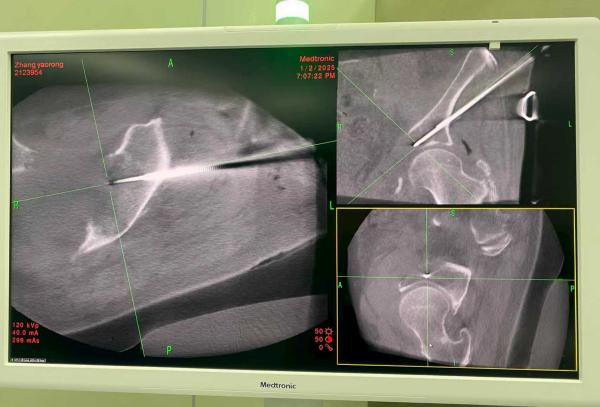

边界清晰,治疗更安全:利用冷冻形成的可视化“冰球”边界,医生能在术中毫米级精确控制消融范围。这一特性尤其适用于毗邻脊髓、大血管的脊柱、骨盆肿瘤,实现了在“生命禁区”内的精准适形治疗,将邻近神经损伤风险降低了60%以上。

团队已建立涵盖患者筛选、术前3D规划、术中实时导航(如O臂导航)及术后随访的全流程标准化体系。有力推动了我院骨肿瘤多学科诊疗(MDT)中心的建设与发展,整合了骨科、肿瘤内科、影像科、疼痛科等多学科力量,为复杂病例提供最优解决方案。这项“冰与火之歌”不仅为无数陷于剧痛与绝望中的骨肿瘤患者带来了新的生机,也成功开创了骨与软组织肿瘤微创治疗的新赛道,彰显了我院作为国家医学中心创建单位在攻克疑难重症领域的引领实力与担当。